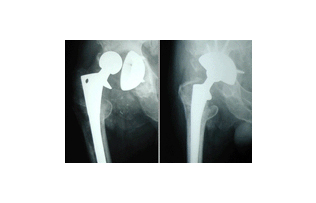

고관절 수술 후 회복 기간은 환자의 상태와 수술 방법에 따라 크게 달라집니다. 일반적으로 고관절 수술에는 두 가지 주요 유형이 있습니다. 첫째는 관절경 수술로, 최소 침습적으로 문제를 해결하는 방법입니다. 이 경우 회복 기간이 짧을 수 있습니다. 둘째는 관절 치환술로, 고관절을 인공 관절로 대체하는 수술입니다. 이 수술은 보다 복잡하며, 회복 기간이 상대적으로 더 길어진다는 특징이 있습니다.